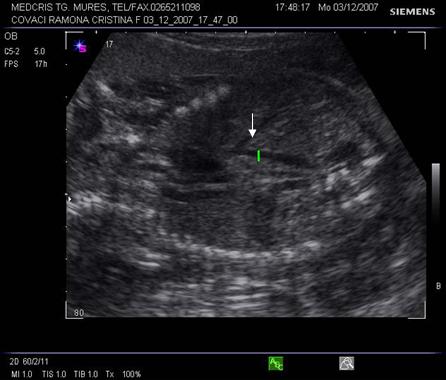

Fig. nr.176. Planul 0 de sectiune transversala ptr examinarea cordului, se incepe cu abdomenul , in care se remarca stomacul si aorta ( cu o sageata ) alaturi spre dreapta , vena cava inferioara ( cu doua sageti )